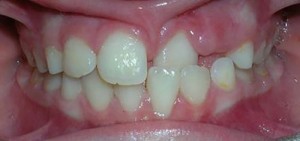

Authors: Andrea Fama , Davide Cavagnetto, Andrea Abate, Andrea De Filippis, Eleonora Mainardi, Luca Esposito

The term dilacerated refers to a dental element that has an alteration of the axial inclination of the crown with respect to the root. Dilaceration can occur at the crown-root junction with...